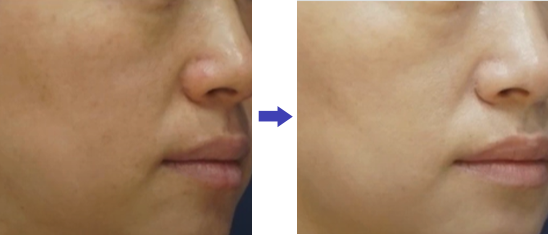

ลดความหย่อนคล้อย

ลดความหย่อนคล้อย